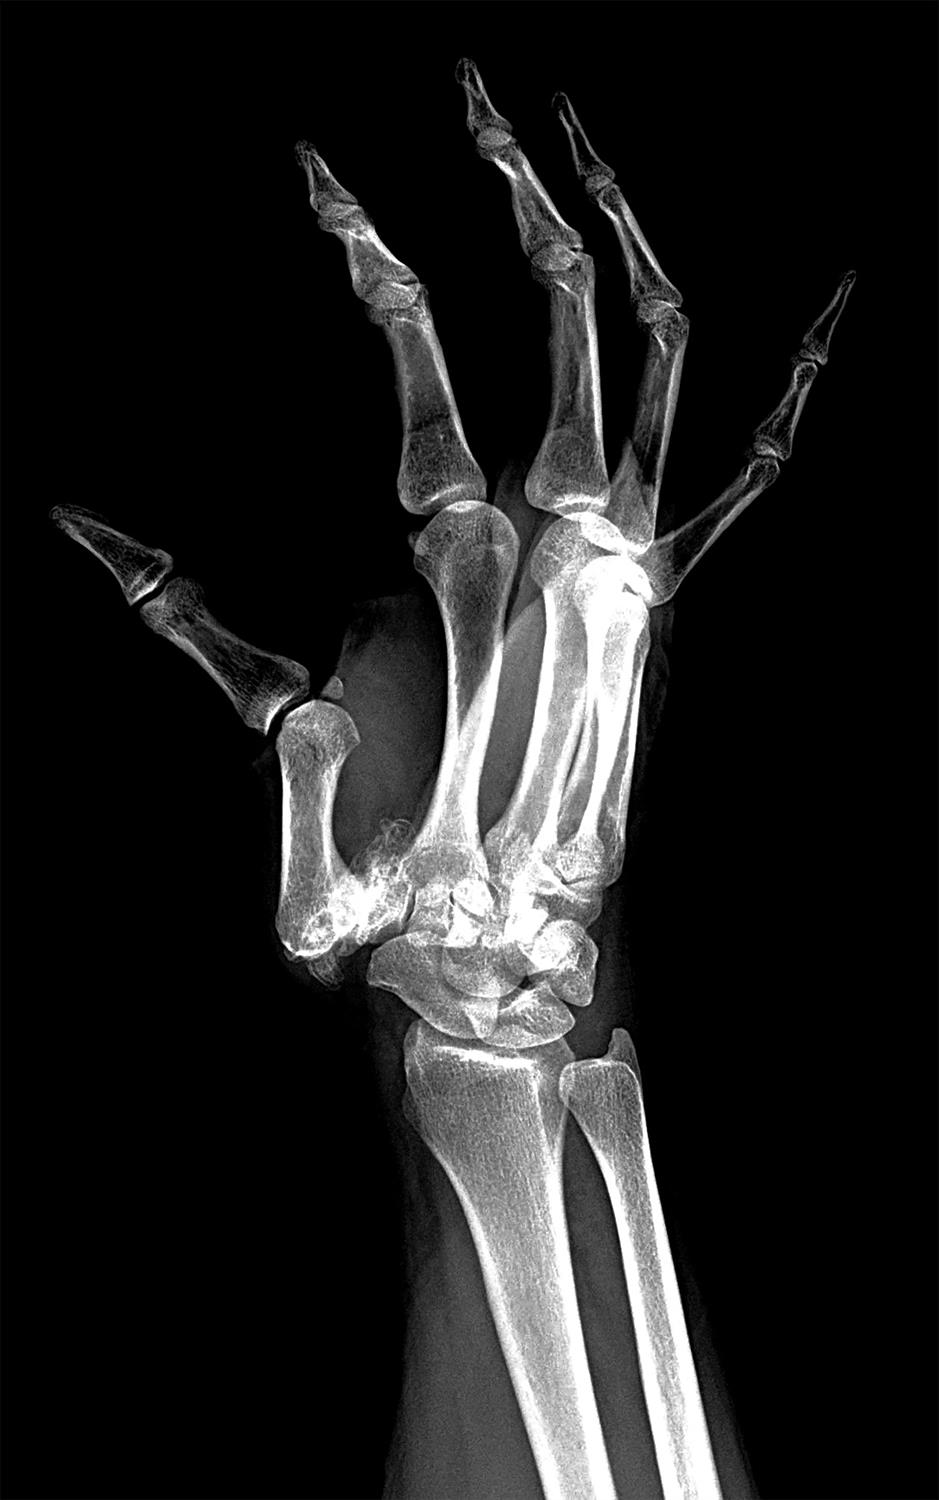

the thumb cmc joint has been reported as the most painful joint when compared to other hand joints affected by oa. basilar thumb arthritis, also referred to as trapeziometacarpal (tmc) arthritis, is a common degenerative. the basal joint at the base of the thumb — or thumb cmc joint — is located near the wrist and at the fleshy part of the thumb. stt arthritis often found with concomitant basilar thumb arthritis. like other forms of osteoarthritis, basal thumb arthritis develops when cartilage on the surfaces of the bones that meet at the joint wears away and the. up to 15% of the population older than 30 years suffers from symptomatic thumb carpometacarpal. arthritis of the dip and pip joints are very common forms of osteoarthritis seen in the hand and can be associated with pain and deformity.